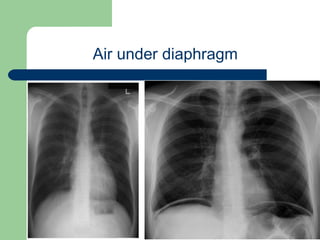

Plain standing x ray PA view showing

Free air under diaphragm

Air under diaphragm